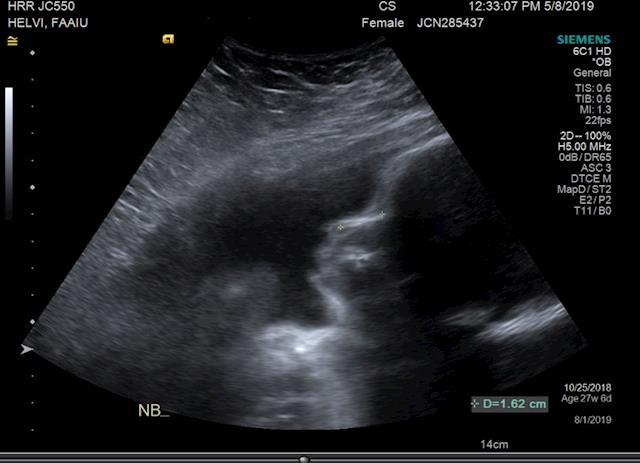

Thank you to everyone who has donated thus far! We are so overwhelmed by the outpouring of love & are so appreciative. So we just thought we’d update with a photo of our little one.